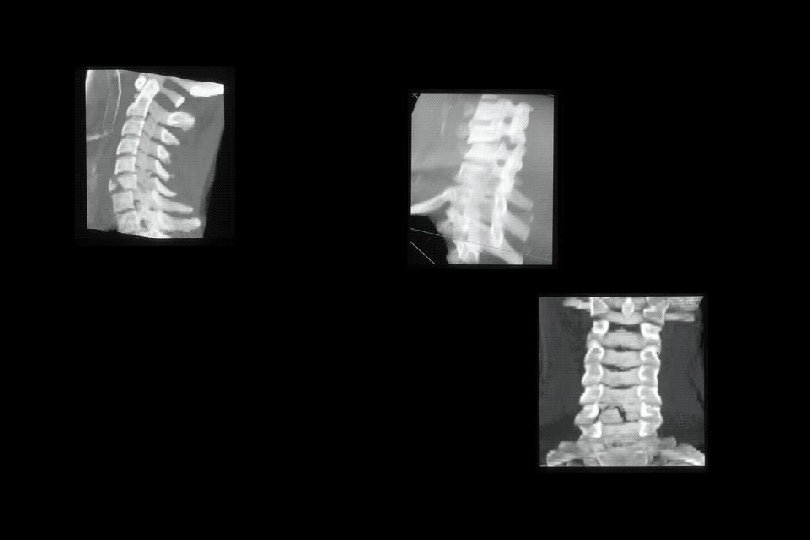

Servikal omurga yaralanmaları • Atlas kırıkları (Jefferson); Ön ya da arka kol kırıklarıdır. Mekanizma aksiyal yüklenmedir. • C 1 subluksasyon: Çoğunlukla çocuklarda görülür. Ağız açık dens grafilerinde tanınabilir. Odontoid C 1’in her iki lateral “mass”’ından eşit uzaklıkta değildir. • C 2 odontoid dislokasyon: Transvers ligaman yaralanmıştır. C 1 ön kolu ile odontoid arasında 3 mm. den fazla mesafe vardır.

Servikal omurga yaralanmaları • C 2 odontoid kırıkları – Tip I: Odontoid uç kırığıdır ve çoğunlukla stabildir. – Tip II: Odontoid basisinde oluşur ve genellikle anstabildir. Çocuklarda 6 yaşına dek epifizin görülebildiğini ve bunun kırık olmadığını hatırlamak gereklidir. – Tip III: Omur cismine uzanan odontoid kırığıdır.

Servikal omurga yaralanmaları • C 2 arka eleman kırıkları: “Ası” kırığı da denir. Mekanizması genellikle fleksiyon-aksiyal yüklenme veya fleksiyon-rotasyon şeklindedir. • C 2 -C 7 arası kırıklar ve kırık-dislokasyonlar: Çeşitli mekanizmalar rol oynar; fleksiyon-aksiyal yüklenme, ekstansiyon-aksiyal yüklenme ve fleksiyon-rotasyon. Kırık anstabil ise aşağıdaki özelliklerden biri ya da birkaçı mevcuttur; – Arka ve ön elemanlar birbirlerinden ayrılmıştır – 3 mm. den fazla kayma vardır. – İki omur arasında 11°den fazla açılanma vardır.